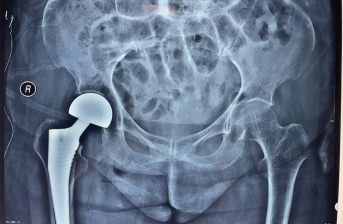

术前x线片 术后x线片

一切准备就绪后,在麻醉科的鼎力协助下,骨科主任陈天健、副主任黄小俊带领手术团队先后顺利为两位老人实施髋关节置换术。术后,老人平安回到病房。

医务人员密切关注两位老人术后的恢复情况,精心护理,指导康复锻炼。在患者及家属的积极配合下,术后24小时,两位患者便可扶助行器行走。

此次治疗,运用了ERAS理念,术前对患者积极进行了康复干预,根据术前了解、术中观察,为患者制定了个性化的康复治疗计划,患者入院后一周之内完成了手术治疗,术后第三天可以下地自主行走,术前、术后康复的无缝衔接,为患者的功能恢复提供了有力的保障,达到了早期手术、快速康复、减轻疼痛的目的,有效减少了骨折所带来的并发症,降低了致死率、致残率。